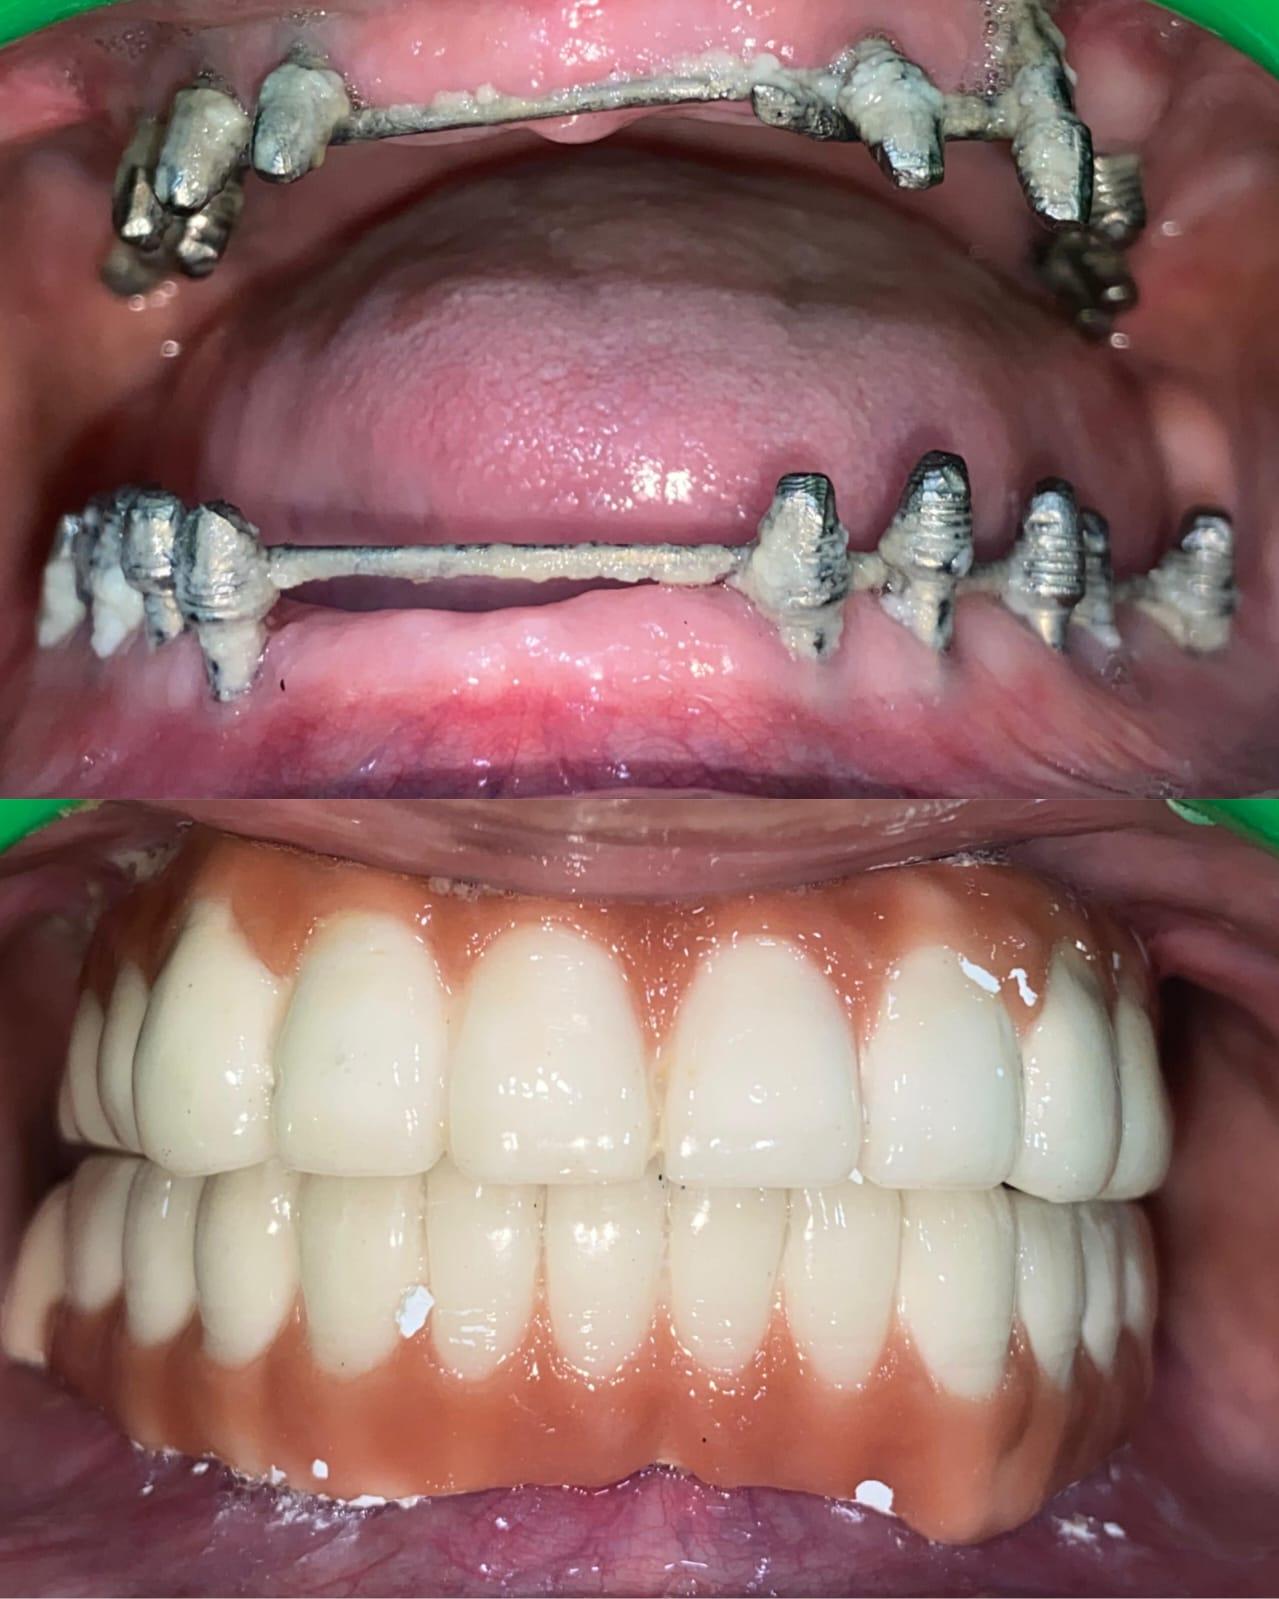

Unlock the power of syncrystallization, the revolutionary technique ensuring rigid splinting of implants through precise intraoral welding.

Become a Master in Prosthesis with expert training in immediate loading, full-arch rehabilitations, and screw-retained prosthetics. Learn precise occlusal corrections, biomechanics, and functional aesthetics for long-term success.

Our workshop emphasizes immediate loading protocols with real patient cases. You'll witness and assist in live surgeries, not simulations. Every participant gets hands-on experience with a minimum of 5 live implant cases, combined with advanced prosthetic planning and lifetime mentorship support. We are the only workshop in india that provides hands-on experience with intra oral welding.